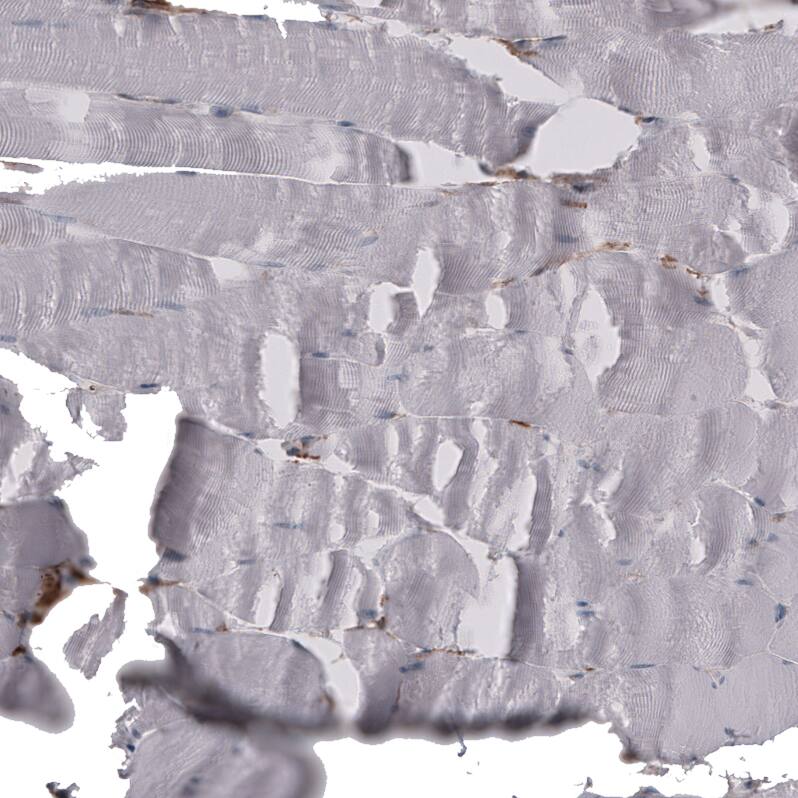

Staining of human skeletal muscle shows no positivity in myocytes as expected.